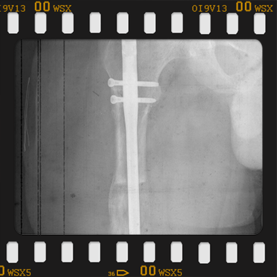

Görüntüleri büyütmek için üzerine tıklayınız.

Görseli büyütmek için üzerine tıklayınız. Görseli büyütmek için üzerine tıklayınız. Radyografi görseli büyütmek için üzerine tıklayınız. Radyografi görseli büyütmek için üzerine tıklayınız. Radyografi görseli büyütmek için üzerine tıklayınız.